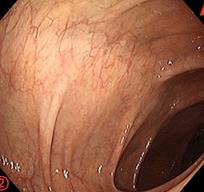

摘要:目的 探讨利那洛肽联合西甲硅油与复方聚乙二醇电解质散(PEG)对便秘患者肠道清洁效果的有效性和安全性。方法 采用前瞻性随机对照试验,通过单盲法,纳入2023年4月-2024年8月于该院消化内镜中心行结肠镜检查的便秘患者383例,随机分为常规组(128例)、实验A组(128例)和实验B组(127例)。常规组采用3 L PEG(Ⅰ)溶液,实验A组采用290 μg利那洛肽 + 2 L PEG溶液,实验B组采用290 μg利那洛肽 + 30 mL西甲硅油+2 L PEG溶液。比较3组患者的肠道准备效果[Boston肠道准备量表(BBPS)评分和去泡效果]、病变检出率、首次排便间隔时间、排便次数、盲肠插管成功率、进镜时间、退镜时间、不良反应发生率和重复检查意愿等。结果 3组患者BBPS评分比较,差异无统计学意义(P > 0.05);实验B组的去泡效果评分明显低于常规组和实验A组,差异均有统计学意义(P < 0.05);实验B组的病变总检出率和息肉检出率明显高于常规组和实验A组,差异均有统计学意义(P < 0.05);常规组的首次排便间隔时间明显长于实验A组和实验B组,差异均有统计学意义(P < 0.05);3组患者排便次数比较,差异无统计学意义(P > 0.05);3组患者盲肠插管成功率均为100.0%,进镜时间相当,差异均无统计学意义(P > 0.05);实验B组的退镜时间明显短于常规组和实验A组,差异均有统计学意义(P < 0.05);常规组腹胀腹痛发生率和不良反应总发生率明显高于实验A组和实验B组,差异均有统计学意义(P < 0.05);常规组重复检查意愿率明显低于实验A组和实验B组,差异均有统计学意义(P < 0.05)。结论 290 μg利那洛肽联合30 mL西甲硅油与2 L PEG溶液方案在便秘患者肠道准备上具有优势,较3 L PEG溶液和290 μg利那洛肽+2 L PEG溶液方案,可获得更好的肠道清洁效果,且安全性和患者重复检查意愿率高,可作为便秘患者肠道准备的推荐方案。